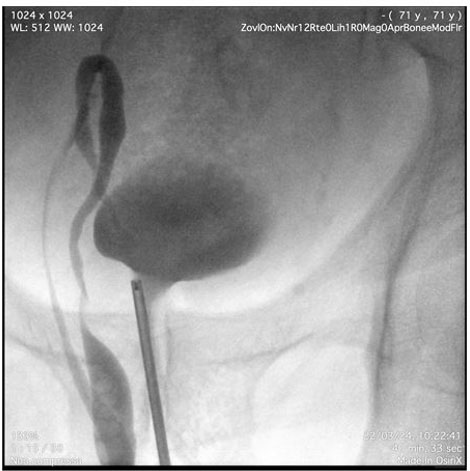

Pyelography was performed using an 8 Ch ureteroscope. After inserting the instrument into the bladder, the right ureteral meatus was identified and pyelography was performed with an open-ended catheter. The tortuosity of the ureter was confirmed, describing a double loop into the scrotum (Figure 2 and Figure 3). After identifying the renal pelvis, approximately in the right iliac fossa, a 6 Ch monoJ ureteral catheter was positioned.

Figure 2: Pyelography.